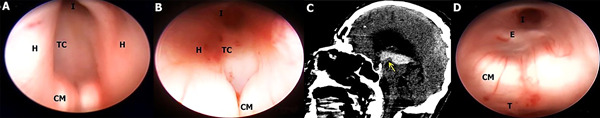

En este estudio fueron halladas 10 variedades anatómicas del piso anterior del tercer ventrículo, las cuales son en orden de frecuencia: piso opaco o grueso 54,90% (Figura 1), piso parcialmente borrado 29,41% (Figura 2), intervalo prepontino pequeño 23,53% (Figura 3), piso estrecho 17,65% (Figura 4 A-B), piso herniado 17,65% (Figura 5), piso delgado 11,76% (Figura 6), basilar elevando el piso 1,96% (Figura 4C-D), adherencias interhipotalámicas 3,92% (Figura 7), fenestración espontánea 1,96% (Figura 8), y piso sin reparos anatómicos 1,96% (Figura 9). Las primeras 7 según la descripción de Sughrue, a la cual se sustituye banda premamilar por adherencias interhipotalámicas, descriptas por Phillips4, fenestración espontánea al hallarse ausencia de PTV u ostomía espontánea como en la Fig. 8, reportada por Parmar5, y se introduce otra categoría no reportada, piso sin reparos anatómicos cuando no se pueden diferenciar los cuerpos mamilares ni el receso infundibular. En la mayoría de los casos se detectaron 2 o más variedades.

Figura 6: A; Hombre con hidrocefalia crónica del adulto. El piso es traslúcido y los CM y el complejo basilar se pueden visualizar con facilidad, disminuyendo el riesgo de injuria vascular. Cuerpos mamilares de tipo Split, separados. B; Otro caso de hidrocefalia crónica del adulto con falla de TVE que se reinterviene endoscópicamente, donde se evidencia ostoma pequeño en TC, el cual es tan delgado que permite ver la arteria basilar y sus ramas ampliamente, con CM separados. C-D Mujer con hidrocefalia congénita, con disfunción de DVP, con un piso notoriamente delgado a través del cual se identifican todas las estructuras de la cisterna interpeduncular y prepontina, incluido todo el recorrido de la AB y cerebrales posteriores, el tercer par craneal izquierdo y el puente.

AB arteria basilar; AP arterias perforantes; CM cuerpo mamilar; CP Cerebral posterior; D dorso selar; H hipotálamo; I Receso infundibular; Os ostoma; Q quiasma óptico; P puente; T tegmentum mesencefálico; TC Tuber cinereum.